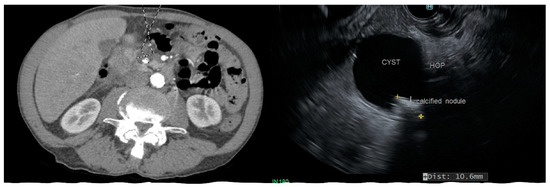

Cyst morphology can provide some insights into the type when characteristic features are present. SPN are characterized by the presence of solid components in the form of a mural nodule. A noticeable feature of SCA, found in about a quarter of cases, is the presence of calcification within the cyst, and this is distinct from the peripheral calcification that can be seen in MCN and SPN (Figure 4). This is sometimes referred to as a “central scar.” Side-branch and mixed-type IPMN are multiloculated and appear as clusters, while main-duct IPMN usually does not demonstrate a prominent cyst but are seen on imaging as a diffuse dilation of the main pancreatic duct.

Figure 4.

MRI and endoscopic ultrasound demonstrating a solid pseudopapillary neoplasm involving pancreatic tail with a regional lymph node involvement.

SPN: SPN are low-grade malignant neoplasms and usually run an indolent course. However, they carry the risk of metastatic spread, and liver and peritoneal deposits may be seen in 5–15% of cases (Figure 4) [17]. SPN is often diagnosed in young adults and are commonly present with an abdominal mass or abdominal pain, and are less commonly asymptomatic [18]. They are often well encapsulated and can potentially be cured with resection. Survival following surgical resection is non-inferior to people without SPN.